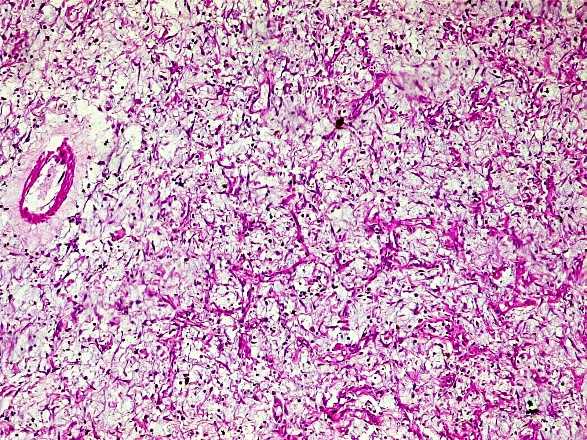

Histological examination at low magnification showed moderately dense cellular areas consisting of short bundles of spindle-shaped cells concentrically wrapped around capillaries. The chorion was rather loosely edematous, fibromyxoid, reworked by hemorrhagic infarction and a marked polymorphic inflammatory infiltrate with numerous eosinophilic polynuclear cells. The contralateral mucosa was regular and partially abraded (Figure 2).

Histological examination of the sections showed a partially abraded, congested intestinal mucosa overlying a fibrous lesion with fibroblasts organized in short bundles. There was associated edema, vascular congestion, hemorrhagic suffusion, and a polymorphous inflammatory infiltrate with numerous eosinophilic polynuclears (Figure 3).

Microscopically, the mucosa was congested, with regular glands and no atypia. The submucosa showed abundant fibrous tissue consisting of spindle-shaped cells organized in short bundles. The stroma was loose edematous fibromyxoid with congested vessels and areas of hemorrhagic suffusion. There was an inflammatory infiltrate of lymphocytes and numerous eosinophilic polynuclear cells (Figure 4).